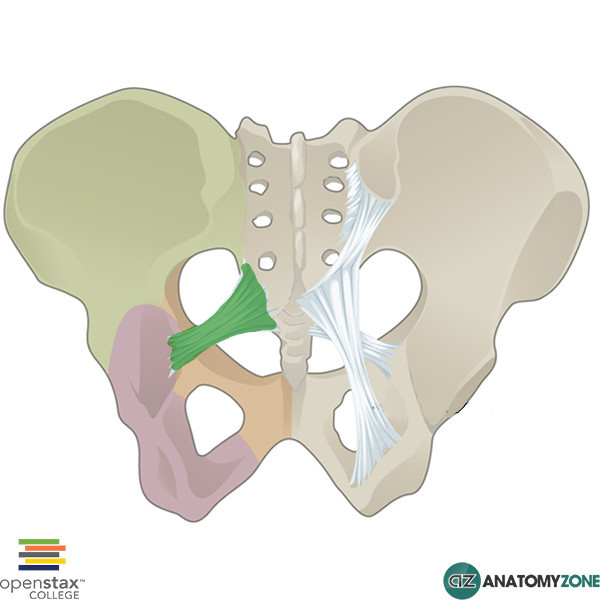

What is this structure?

Sacroiliac ligament

What is this structure?

Sacrotubular ligament

What is this structure?

Sacrospinous ligament